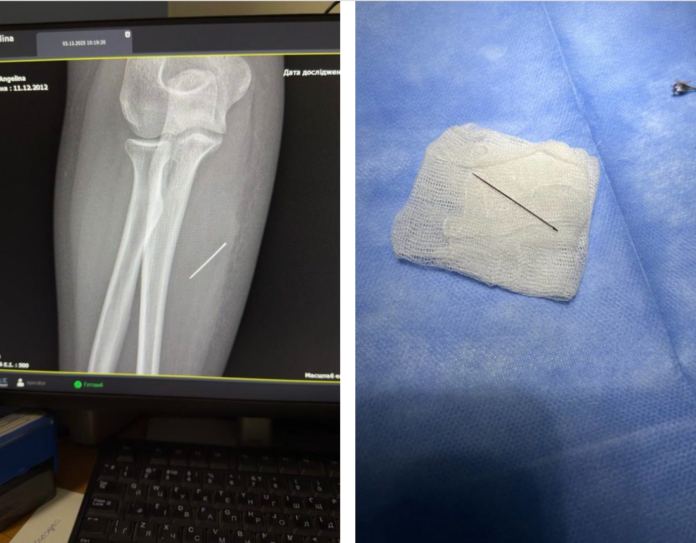

За тиждень голка мігрувала глибше. Рентген показав, що вона зайшла під кутом 45 градусів і застрягла в товщі м’яза. Подальше зміщення могло призвести до ушкодження судин або нервів.

Під час операції лікарям було критично важливо витягнути голку точно за траєкторією входження, аби вона не зламалася. За допомогою рентген-навігації хірурги точно визначили її місце, зробили мінімальний розріз і безпечно вилучили сторонній предмет.